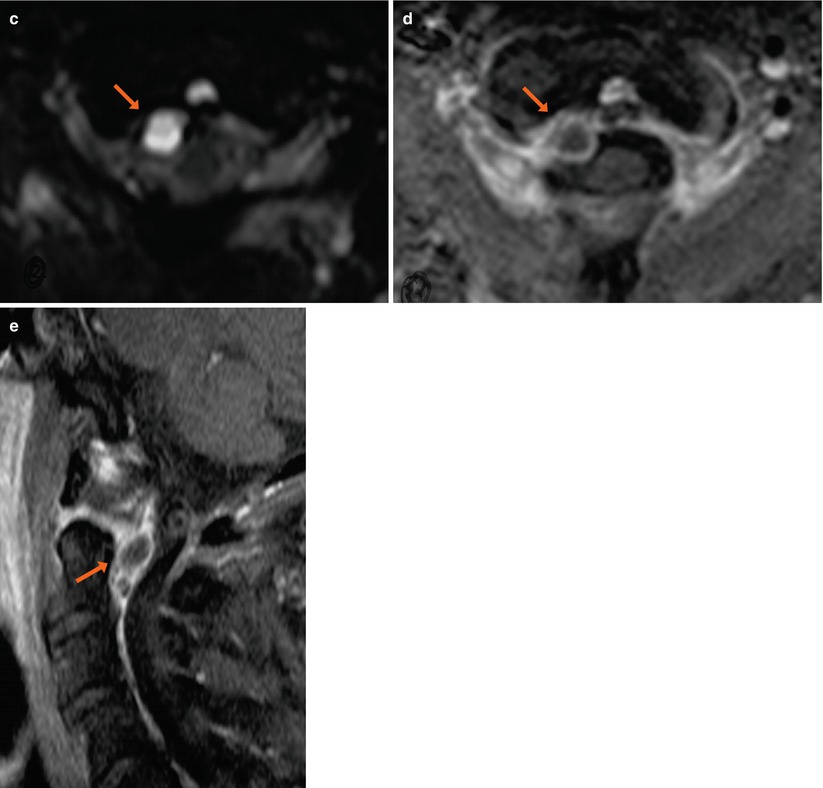

Synovial cyst with spinal stenosis synovial cyst with spinal stenosisSynovial spinal cysts facet ganglion juxta left sydney axial arrows causing narrowing demonstrates significant stenosis sided shows right white Spinal synovial cyst.